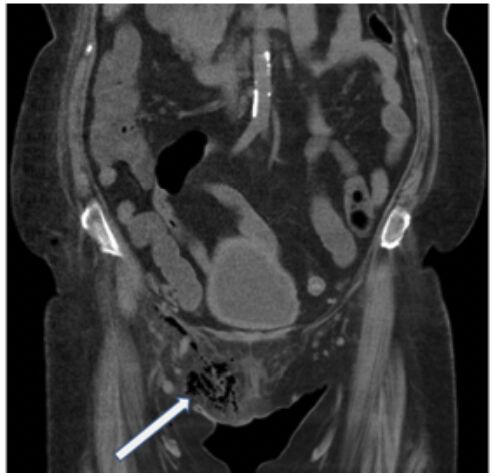

50.74歲楊女士這一星期來左下腹疼痛越來越厲害到急診求診,其過去病史有糖尿病、高血壓病及大腸憩室炎;急診的生命徵象穩定,但體溫為38.5℃;其他的臨床症狀包括食慾變差(anorexia)、噁心(nausea)及有腹 瀉(diarrhea)的情況。理學檢查發現左下腹疑似有摸到硬塊且有壓痛合併局部性的腹膜炎(localized peritonitis)之情形,抽血檢查發現WBC:19,310/mm3,neutrophil:86.1%,CRP:196 mg/L,腹部的電腦斷 層如附圖,則最可能的診斷為何?(A)缺血性腸壞死(ischemic bowel) (B)乙狀結腸腸扭轉(volvulus) (C)乙狀結腸憩室炎破裂併膿瘍(ruptured sigmoid diverticulitis with abscess) (D)空腸腸繫膜膿瘍(jejunal mesenteric abscess)